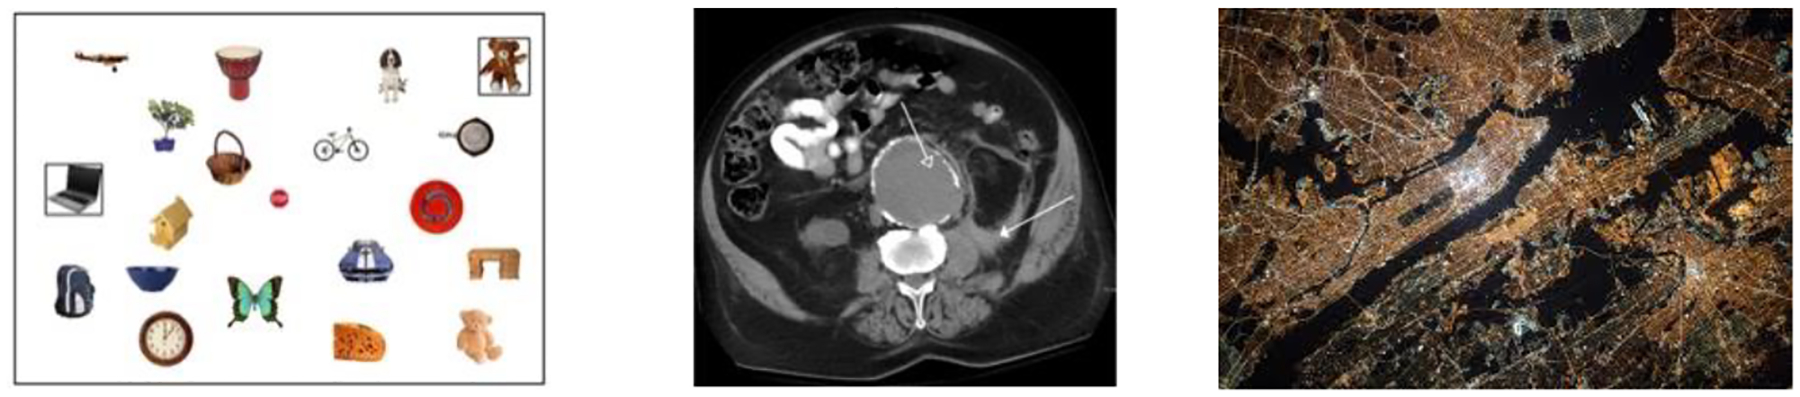

Visual search professionals frequently examine complex images in which they must locate and identify anomalies (e.g., tumors or lesions in medical images, hostile territories in maps) indicating the presence of important information. This is a difficult perceptual and cognitive challenge that requires years of experience even beyond domain-specific training. We developed a laboratory analogue of this task to examine how people development expertise over time and the changes that occur in visual scanning behaviors as this expertise accrues. Participants' eyes were tracked as they searched for subtle anomalies during and after different forms of training. Anomaly detection improved with experience and this improvement occurred more quickly in perceptual training conditions. Eye movement analyses revealed that participants' expertise conferred benefits in both scanning and recognition times. These results suggest that simple perceptual training methods can affect both cognitive and oculomotor components of visual search.

Abstract Image